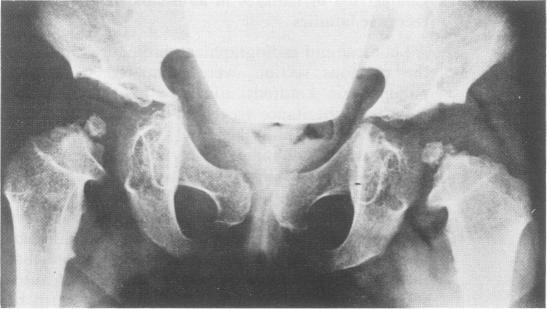

This survey reviews the diagnosis (predominantly radiological) of 32 cases of pseudoachondroplasia from 26 kindreds and illustrates the natural history and varying appearance of the disordered bone growth from infancy to adult life. In addition, an attempt has been made to detect phenotypic differences between autosomal dominant and recessive types (excluding isolated cases), analysing 10 kindreds of dominant inheritance (three in the current survey, seven from published reports) and six of recessive inheritance (three in the current survey, three from published reports). There appears to be no clinical or radiographical feature which clearly distinguishes them, but, using height as a criterion of severity, among those with autosomal recessive inheritance there was a disproportionate number of the most severely affected cases and there also appears to be very little intrafamilial variation. It is possible that pseudoachondroplasia can be subdivided into autosomal dominant mild and severe and autosomal recessive mild and severe, but full delineation must await elucidation of the basic defect at biochemical and molecular levels.

本调查回顾了来自26个家族的32例假软骨发育不全病例的诊断(主要是放射学诊断),并阐述了该疾病从婴儿期到成年期骨骼生长紊乱的自然病史及不同表现。此外,还尝试检测常染色体显性和隐性类型(不包括散发病例)之间的表型差异,分析了10个显性遗传家族(本次调查中有3个,已发表报告中有7个)和6个隐性遗传家族(本次调查中有3个,已发表报告中有3个)。似乎没有能明确区分它们的临床或影像学特征,但是,以身高作为严重程度的标准,在常染色体隐性遗传患者中,受影响最严重的病例比例过高,而且家族内差异似乎也很小。假软骨发育不全有可能可细分为常染色体显性轻度和重度以及常染色体隐性轻度和重度,但要进行全面分类,必须等待在生化和分子水平上阐明其基本缺陷。